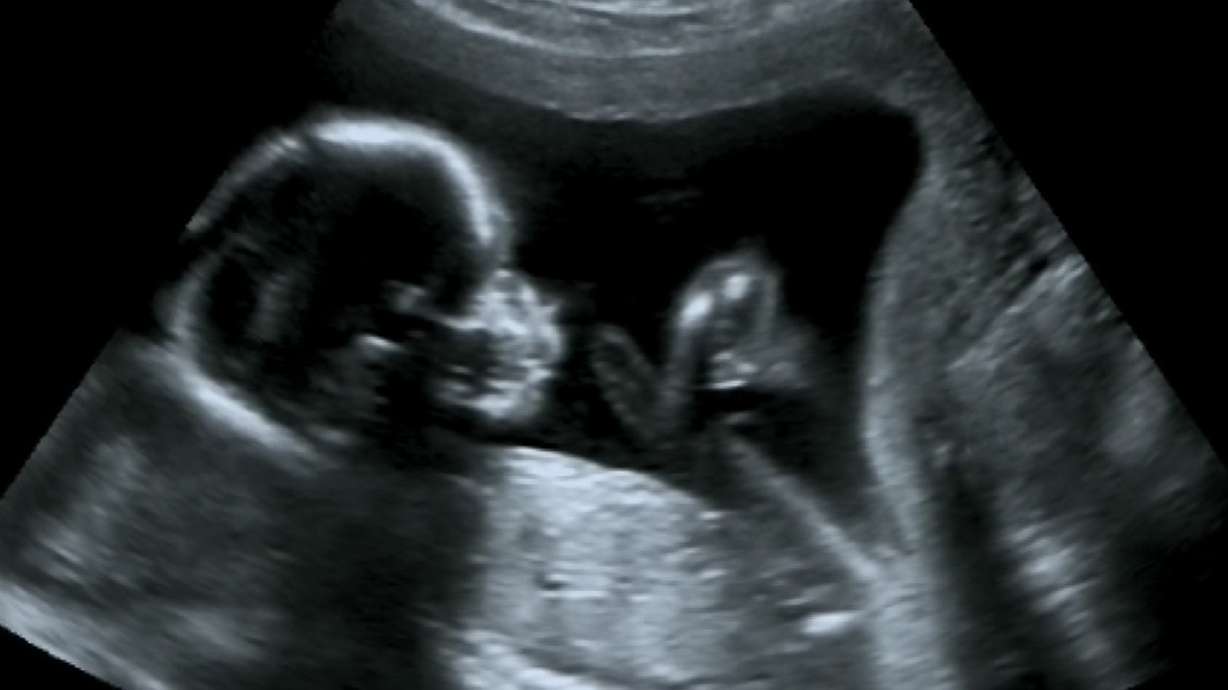

[To read the full story go to DeseretNews.com](<http://www.ksl.com/ad_logger/ad_logger.php?location=http://www.deseretnews.com/article/865585688/The-disputed-science-of-fetal-pain.html&s_cid=ksl-partner&sponsor=Abortion policy and disputed science: How soon do fetuses feel pain?>).